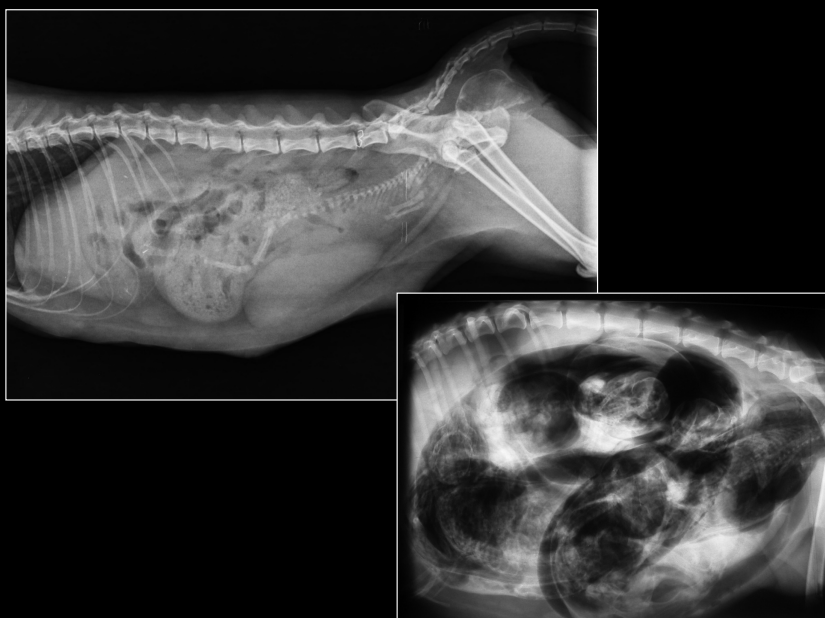

ÚTERO

- Normalmente no se ve.

- Visible cuando distendido: estructuras tubulares tortuosas en abdomen caudoventral.

- Causas:

- Fisiológico: gestación temprana

- Patológico: piómetra, hidrómetra, mucómetra, neoplasia, absceso de muñón

- Gestación: mineralización fetal visible 40–45 días.

- Muerte fetal (Si encontramos gas con los fetos), momificación, distocia (Problemas para el parto).